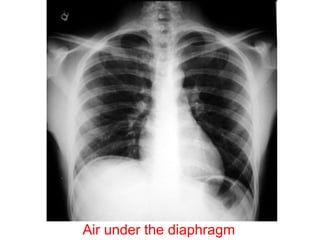

Air under thediaphragm